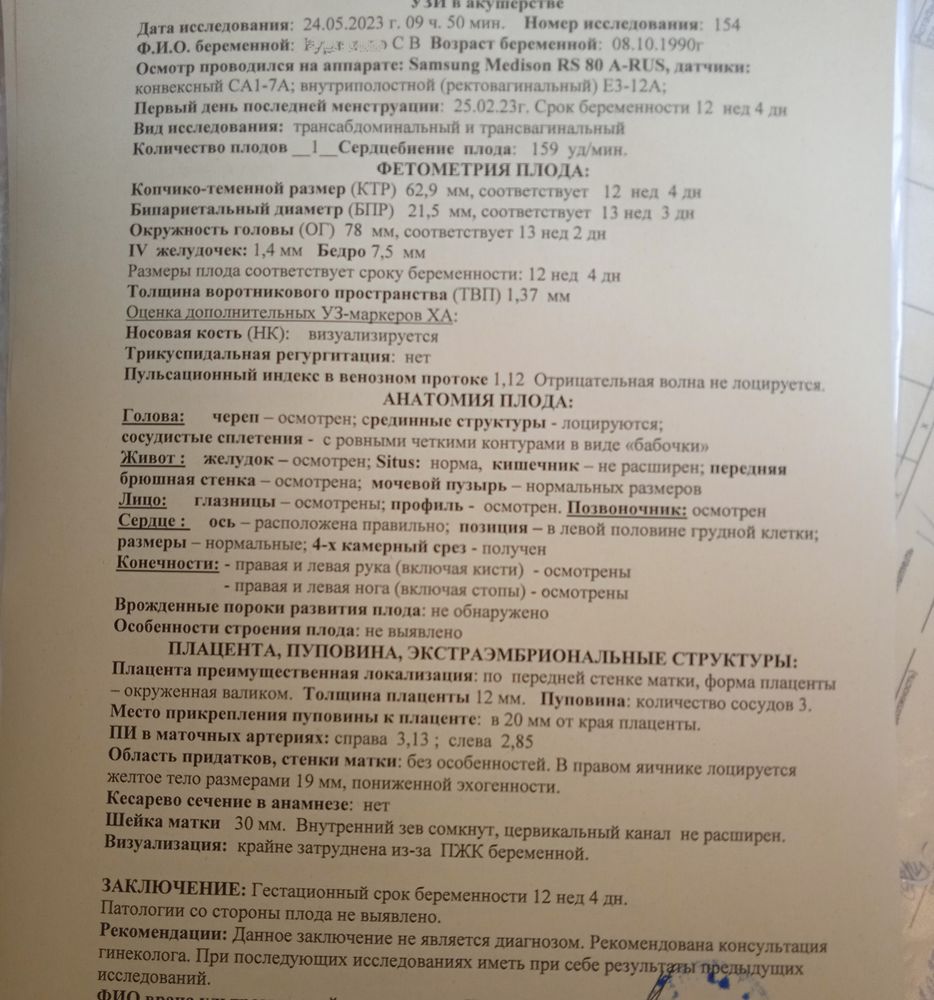

Ксю, вот результат в жц и пометки врача что в норме а что нет🙂кровь норма

Ксю, вот результат в жц и пометки врача что в норме а что нет🙂кровь норма